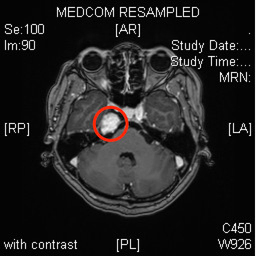

据介绍,41岁的林女士(化名)之前并没有感觉任何不适,在常规体检中发现颅内有个肿瘤,进一步完善磁共振提示,肿瘤位于中颅窝底,并且与颅内最大的血管颈内动脉紧邻

▲mri术前图